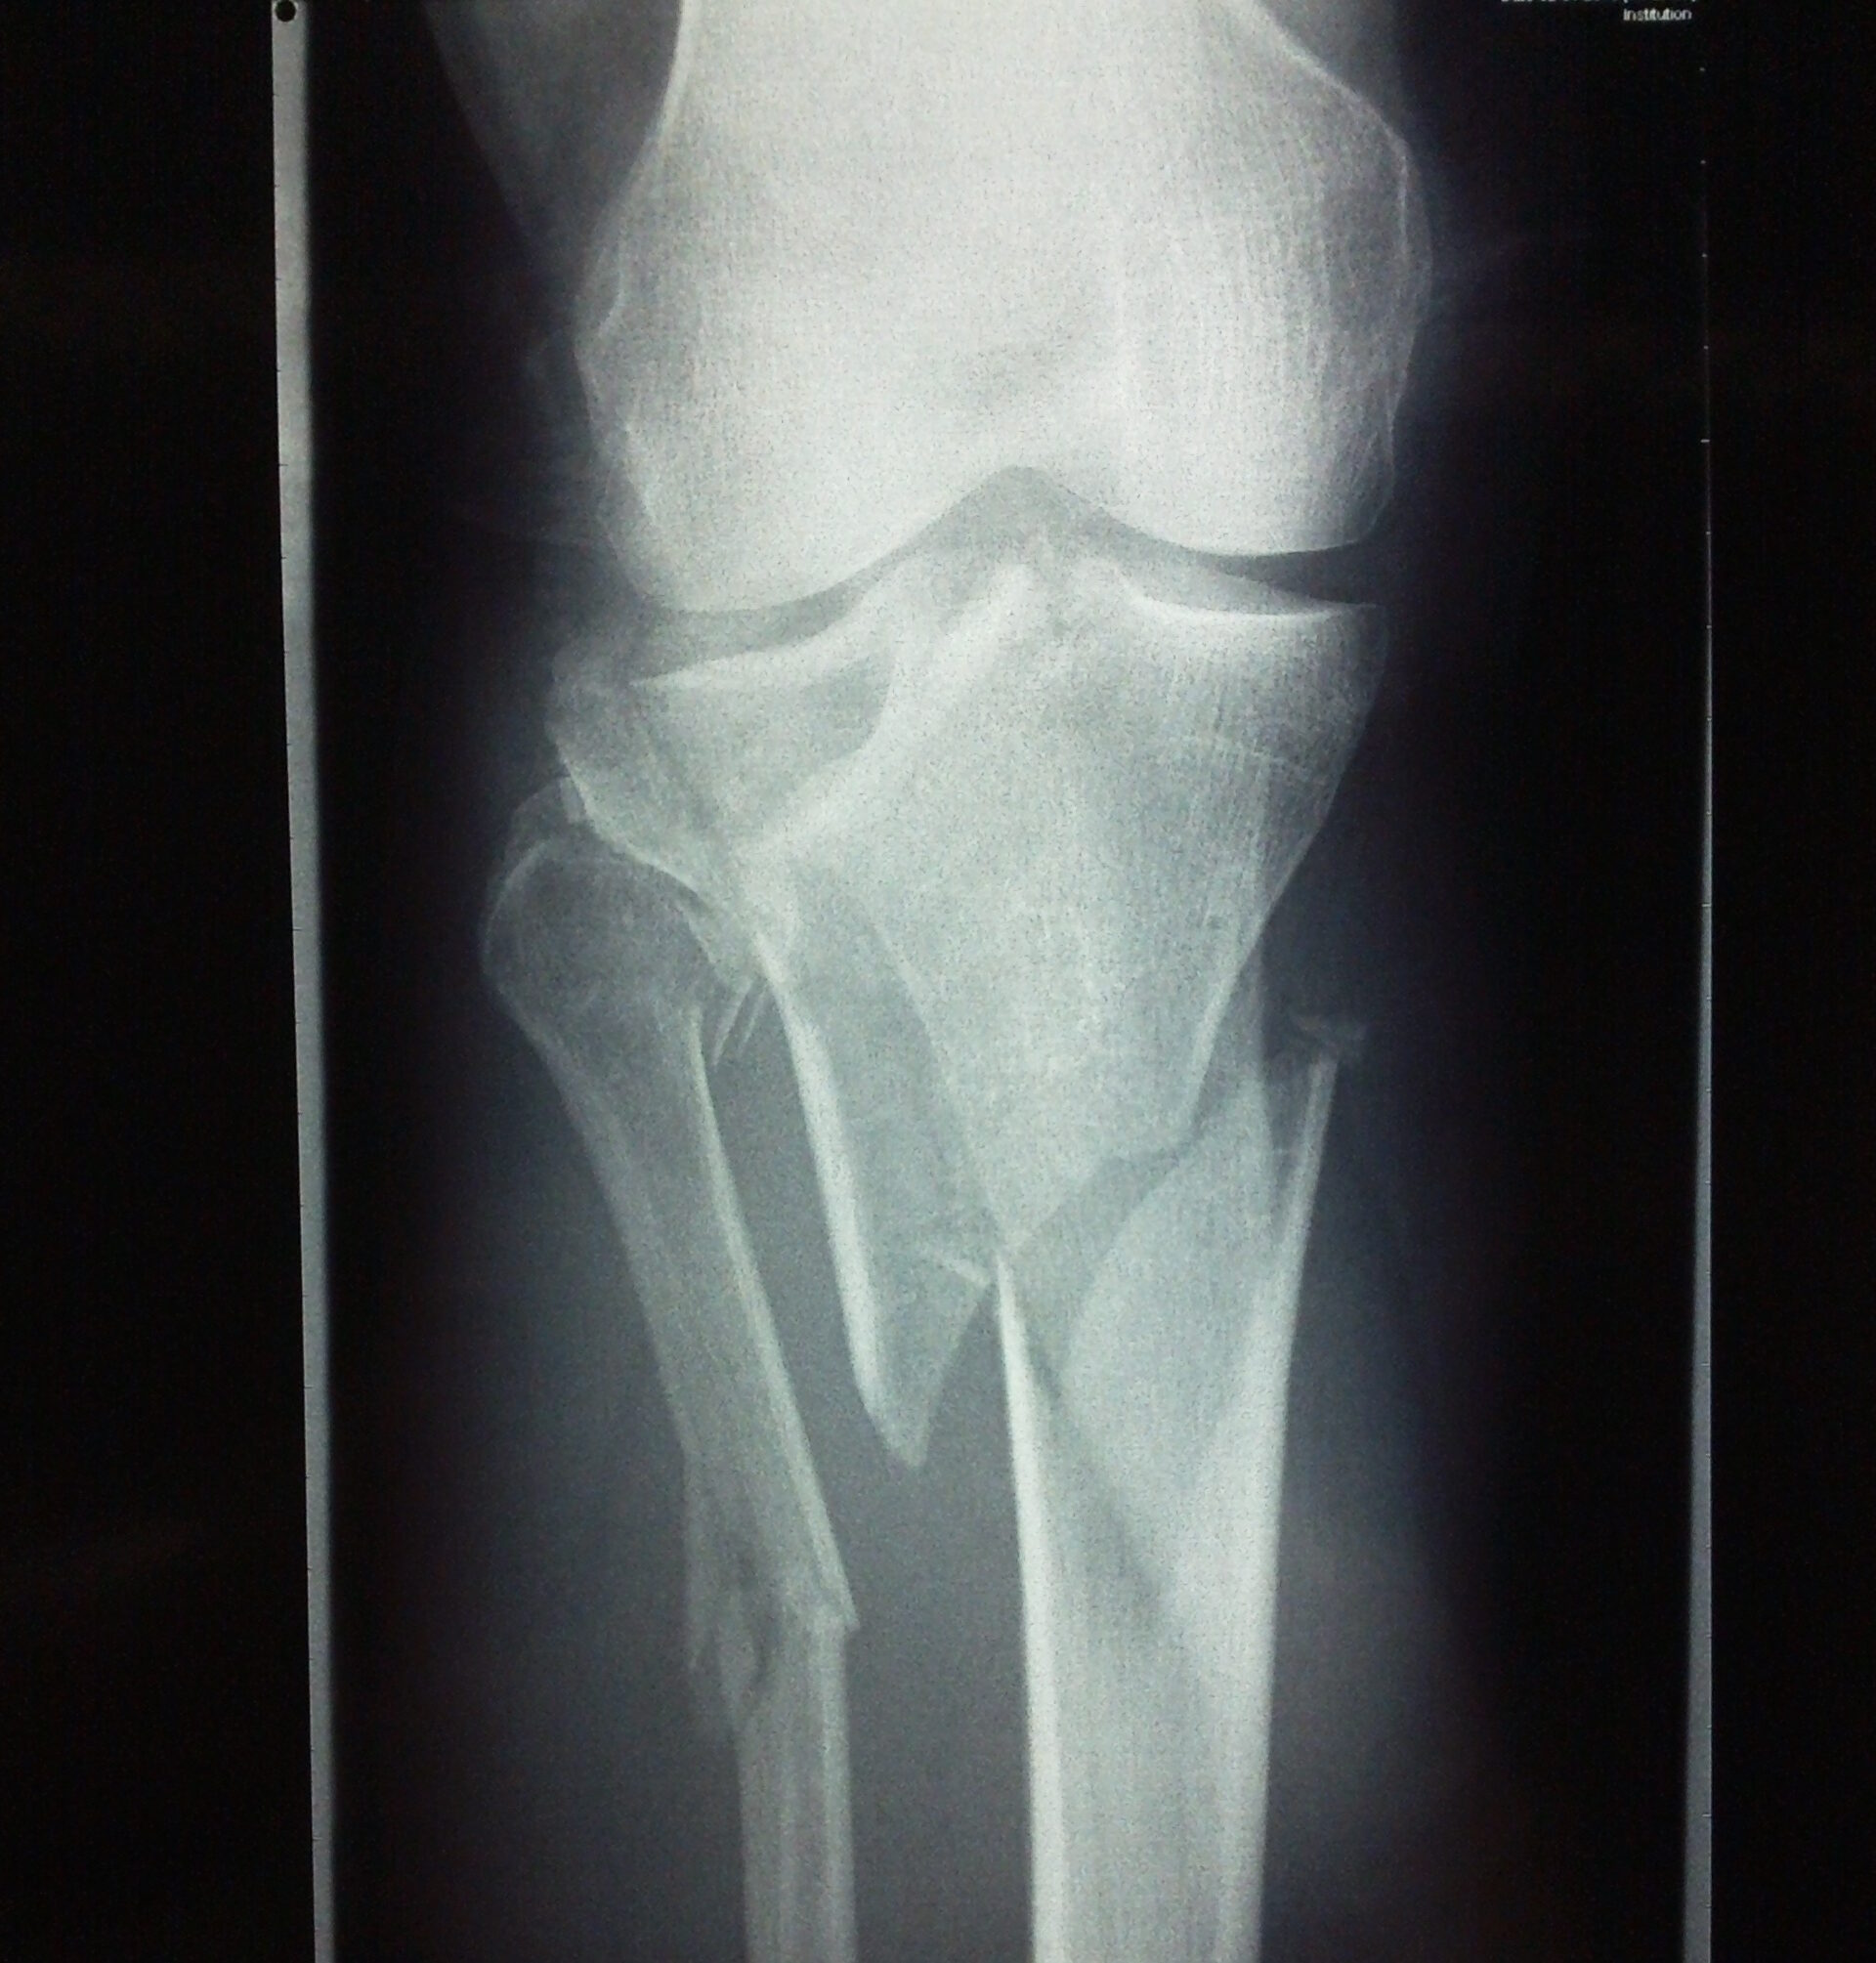

prelom platoa tibije dijagnoza

Neophodni su rendgen snimci AP i lateralni rtg kolena. Daju osnovnu a poekad i dovoljnu informaciju o kakvim se prelomima radi.

Danas se često izvodi i CT snimanje kolena. Posebno ako se planira operacije preloma. Skener daje bolji uvid u konfiguraciju preloma i olakšava planiranje hirurške rekonstrukcije.